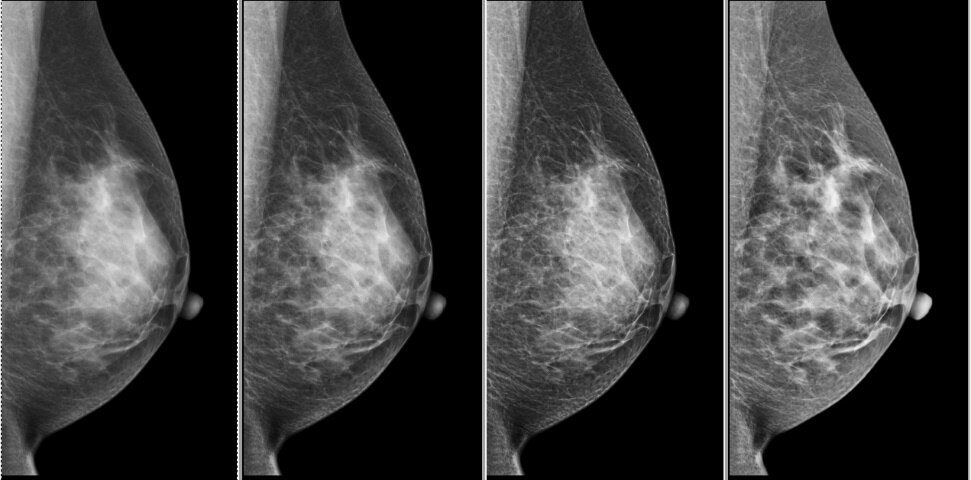

また、フィルム診断からモニタ診断へ移行するため読影に支障がでるのではないかと心配していましたが、Crystal Novaにはつ4つのeContrastレベルがあり読影医の好みに合った画像を提供できるためとても好評でした。

Fig.8 eContrast